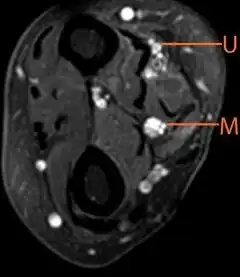

| Multifocal motor neuropathy (with enlargement of the median nerve)-axial plane of T2-weighted scans of forearm | |